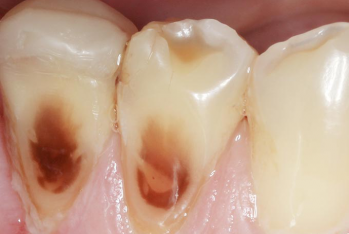

Article réservé à nos abonnés Dépistage des lésions des tissus durs : les formes cliniques les plus fréquemment rencontrées en omnipratique

Dépister les lésions des tissus durs fait partie de la prévention dentaire secondaire. La prévention secondaire consiste à réduire la...